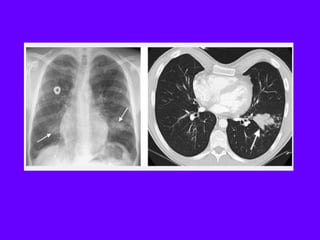

Langerhans Cell Histiocytosis

HRCT Findings

Small peribronchiolar nodules (1-5mm)

Thin-walled cysts (< 1cm),

Bizarre and confluent

Ground glass opacities

Late signs: irreversible / parenchymal fibrosis

Honey comb lung, septal thickening,

bronchiectasis

1 year later

Peribronchiolar Nodules Cavitating nodules and cysts

Langerhans Cell Histiozytosis

Key Features

Upper lobe predominance

Combination of cysts and noduli

Characteristic stages

Increased Lung volume

Sparing of costophrenic angle